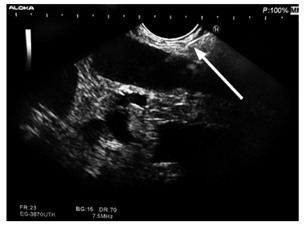

El grupo tratante solicitó endosonografía para ver la posibilidad de toma de biopsia transgástrica de la lesión suprarrenal izquierda. Se realizó endosonografía pancreatobiliar con equipo lineal Pentax y procesador Hitachi, identificando en estación de la unión esofagogástrica una glándula suprarrenal izquierda aumentada de tamaño y con aspecto de masa heterogénea, pero predominantemente hipoecogénica sin una aparente lesión dominante, que llegó a medir hasta 25 mm de mayor dimensión.

Se realizó una biopsia de la masa suprarrenal izquierda guiada por endosonografía por punción con aguja número 22 G, con 7 pases y retirando el estilete, de tal forma que se obtuvo el material adecuado para su estudio.

No hubo complicaciones relacionadas con el procedimiento (Figura 2). El reporte de histopatología fue la presencia de necrosis e inflamación, y a la coloración de Gomori-Grocott se evidenció la presencia de levaduras multigemantes de tamaño variable compatibles con paracoccidioidomicosis. La tinción de Ziehl-Neelsen fue negativa para bacilos ácido-alcohol resistentes y no se evidenció malignidad en la muestra (Figuras 3 y 4). El paciente recibió manejo con anfotericina B hasta completar el esquema y fue dado de alta por mejoría clínica evidente, con manejo ambulatorio con itraconazol y prednisona oral.